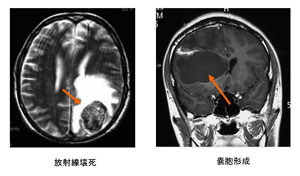

図5

放射線壊死(図5左):放射線壊死は放射線が原因で不可逆的な脳へのダメージがおこる病態です。軽症の場合は副腎皮質ホルモンで軽快しますが、副腎皮質ホルモンが無効の場合には手術で壊死組織を摘出する必要があります。3%以下になるよう放射線の量を決めます。その他、脳動静脈奇形が放射線に脆弱な周辺の脳神経(視神経、聴神経、顔面神経など)に近接していると、これらの神経の障害がでる可能性があります。

放射線壊死以外の晩期放射線障害:また、現在はわかっていない放射線の障害が、数年から10年以上経過して発生する可能性(放射線誘発腫瘍の発生、嚢胞形成、慢性出血など)があります。図5右はガンマナイフ治療後の嚢胞形成例です。これまでの15年間300例のガンマナイフ治療の経験では、いまだ放射線誘発腫瘍の発生はありませんが、長期的にみると数千に一つの割合で発生すると予想しています。